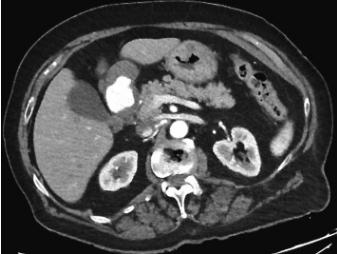

GE后,行静脉造影剂计算机断层扫描(CT)(图2)。CT扫描显示位于胃窦和幽门之间的外生和顶内肿块,在动脉期有明显的造影剂外渗。腹腔内未发现自由空气或腹腔积液的证据。诊断为大GAA。

图2、患者腹部CT,显示对比物明显外渗